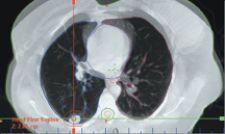

The hypofractionated lung treatments are planned and delivered using images that are generated using a special breath-hold technique. “We use the same breath-hold technique when simulating and when generating the cone-beam CT images with the On-Board Imager just prior to treatment,” said Joseph Ting, Ph.D., chief medical physicist. “The patient holds his breath for 20 seconds at deep inspiration while we are imaging, and then we stop while the patient recovers, and we repeat this three times. That allows us to get a full cone-beam CT data set that shows the lesion very well.”

To position the patient for treatment, the MIMA team generates a new cone-beam CT image using the On-Board Imager and the deep inspiration breath-hold method, and compares the image to the corresponding images from the treatment plan. The On-Board Imager then calculates the amount of couch shift needed in each of three dimensions to fine-tune the patient’s position. “If you can delineate the target very precisely, in this case using cone-beam CT, you can deliver a very large dose in just a few fractions,” Dr. Ting said. “This type of treatment would not be possible without the cone-beam CT imaging that we have at the treatment machine.”